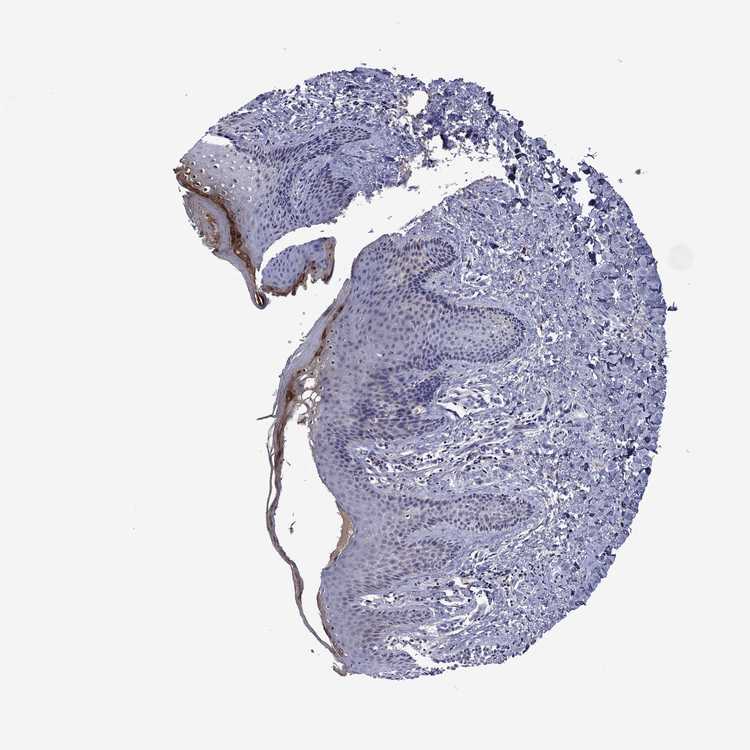

TISSUE PRIMARY DATA SKIN Show tissue menu

SKIN 1 - Antibody stainingi

Antibody staining in the annotated cell types in the current human tissue is reported as not detected, low, medium, or high, based on conventional immunohistochemistry profiling in selected tissues. This score is based on the combination of the staining intensity and fraction of stained cells.

Each image is clickable and will lead to virtual microscopy that enables deeper exploration of all samples and also displays staining intensity scores, fraction scores and subcellular localization as well as patient and tissue information for each sample.

Antibody HPA027241Antibody HPA076029

Langerhans -Not detected

Cells in basal layer Not detected-

Cells in corneal layer Medium-

Cells in granular layer Low-

Cells in spinous layer Not detected-

Endothelial cells Low-

Extracellular matrix Medium-

Fibroblasts -Not detected

Fibrohistiocytic cells Not detected-

Hair follicles Not detected-

Keratinocytes -Medium

Langerhans cells Not detected-

Lymphocytes Not detected-

Melanocytes Not detectedNot detected

Sebaceous glands Not detected-

Vascular mural cells Not detected-